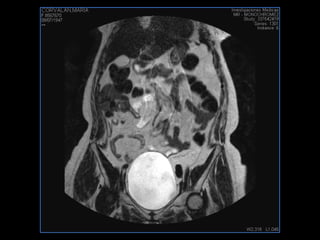

PROTOCOLO pelvis SAG T2, Y FAT SAT (FINOS) AXIAL T1  AX FAT SAT CON   GADOLINIO :  AX T1 Y COR T1 SAT: NO  FASE: RL THK: 3MM  COIL:  GAP: (FACTOR 1.4) 1MM FOV: 40 CM NEX:2 SINCRONIZACION RESPIRATORIA EN 3 O 4 CICLOS ALE